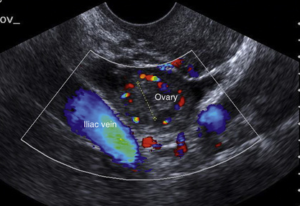

A Pelvic Doppler ultrasound combines traditional pelvic ultrasound imaging with Doppler technology that assesses blood circulation in the pelvic organs. This test helps visualize not only the structure but also the function and blood supply to key reproductive and vascular tissues.

Using sound waves, the Doppler technique can detect:

Blood flow in the uterine and ovarian arteries

Signs of pelvic congestion syndrome

Blockages, clots, or abnormal circulation

Vascular changes related to fibroids, cysts, or endometriosis

Blood supply in pregnancy-related assessments.

Latest Colour Doppler Ultrasound Machines with high-resolution imaging for enhanced diagnostic accuracy.